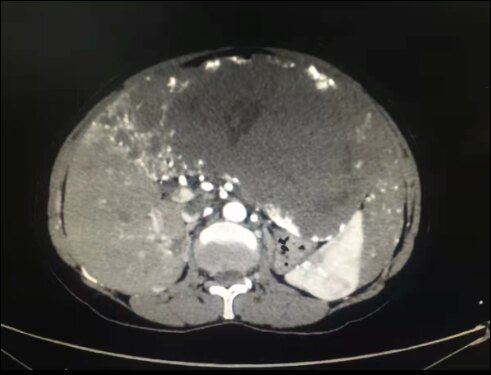

肝海绵状血管瘤,常见于中年病人。多数为单发,也可多发,肝血管瘤在肝右叶比左叶更常见,肿瘤生长缓慢,病程可长达数年以上。瘤体较小时无任何临床症状,增大后主要表现在压迫周围器官,引起上腹部不适。治疗,手术切除是最有效的方法,也可以采取介入栓塞或微波消融的方法。

此患者左肝巨大血管瘤,压迫周围组织,严重影响日常生活,在完善相关术前评估后行扩大左半肝切除。显露采用上腹部倒T切口,控制入肝血流,保留肝中静脉的右侧支,采用CUSA离断肝脏,手术顺利完成。